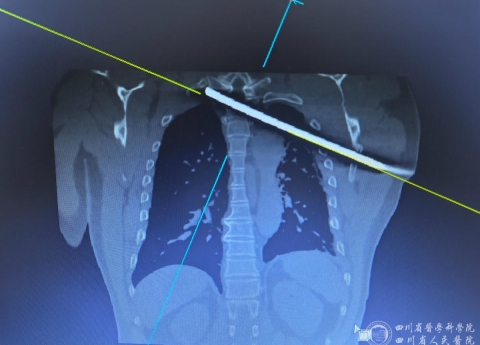

四川观察:男子遭钢筋穿胸 省医院多学科联合开展“毫米级”手术 2025-11-25

四川观察:男子遭钢筋穿胸 省医院多学科联合开展“毫米级”手术

今日头条:钢筋穿胸命悬一线 四川省人民医院多学科专家协作挽救患者生命 2025-11-25

今日头条:钢筋穿胸命悬一线 四川省人民医院多学科专家协作挽救患者生命